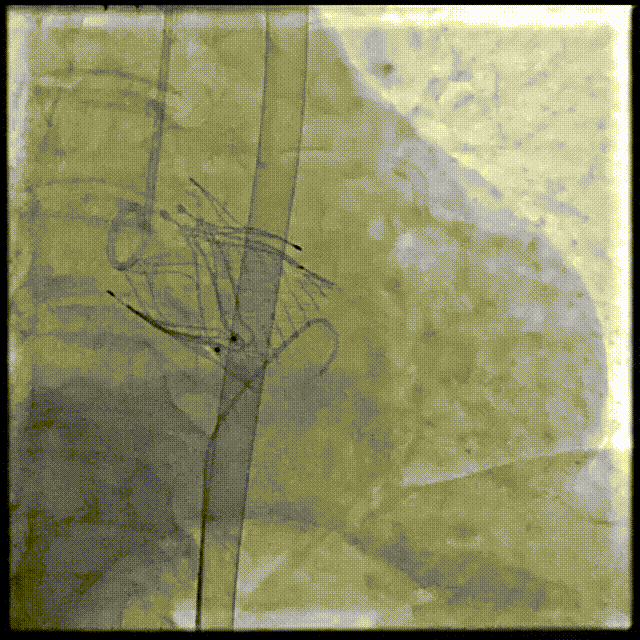

2026年伊始,TaurusTrio经导管主动脉瓣系统在武汉大学人民医院,中国科学技术大学附属第一医院,安徽医科大学第一附属医院,安徽医科大学第一附属医院北区,首都医科大学附属北京安贞医院南充医院,海南省人民医院等多家临床中心成功开展上市后全国首批植入。这不仅是TaurusTrio正式走向广泛临床应用的重要里程碑,更标志着中国单纯主动脉瓣反流介入治疗正式迈入了“心键合璧”的全新纪元。